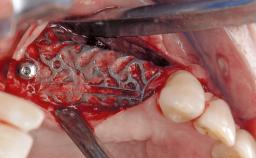

Late Presentation of Peri-Implant Mucositis Requiring Soft-Tissue Augmentation and Esthetic Crown Lengthening at Implant Site 11

Biological or technical complications around implant-supported prostheses place a significant burden on patients as well as the surgical and restorative team. Inflammation of the peri-implant soft tissues is often the first sign that something has gone awry. While there is never a good time for a complication, late presentation of inflammation in the soft tissues around a long-standing prosthesis triggers a period of research and review of the case in order to ascertain the treatment history and its possible contribution to the etiology of the situation. This becomes more complicated in situations where a patient has not received regular maintenance and clinical/radiographical examinations due to personal, financial, or professional reasons. When the complication occurs in the esthetic zone, the complexity of the situation expands exponentially, as the only acceptable outcome in the patient’s eyes will be the maintenance of the esthetics of the prosthesis.

Bone Augmentation -

Soft Tissue Grafting -